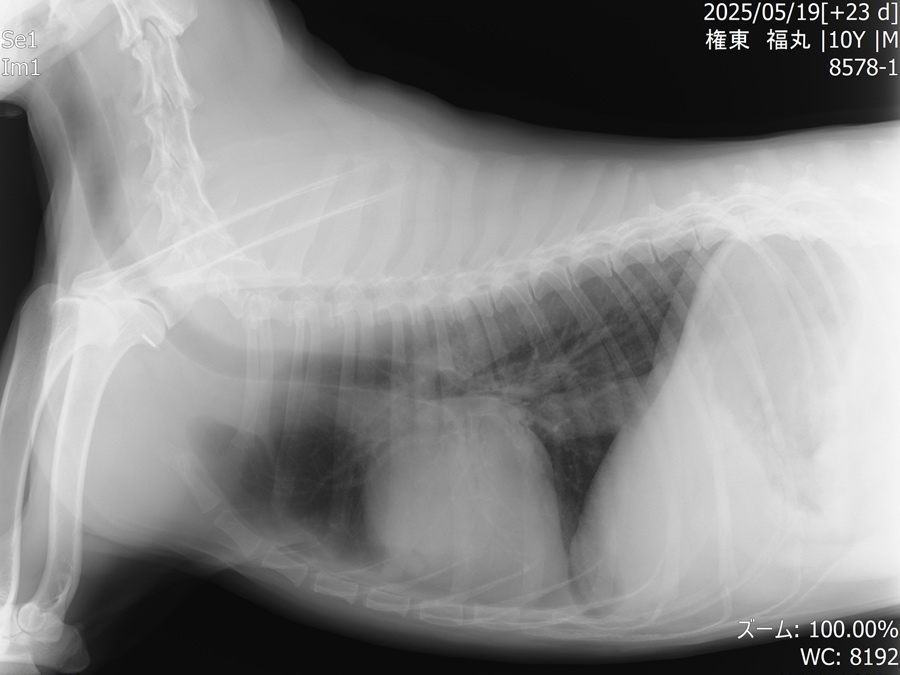

他疾患の手術前検査として実施した胸部レントゲン検査にて、前縦隔部に腫瘤性病変を認めたことから、精査のためCT検査を実施しました。 CT所見より、胸腺腫や異所性甲状腺腫瘍などの腫瘍性疾患が強く疑われたため、胸腔鏡を用いた腫瘤摘出術を行いました。 術前より臨床症状は認められず、全身状態も良好であったため、術後の経過は順調であり、術後2日目に退院となりました。

手術前のレントゲン画像

術後のレントゲン画像写真